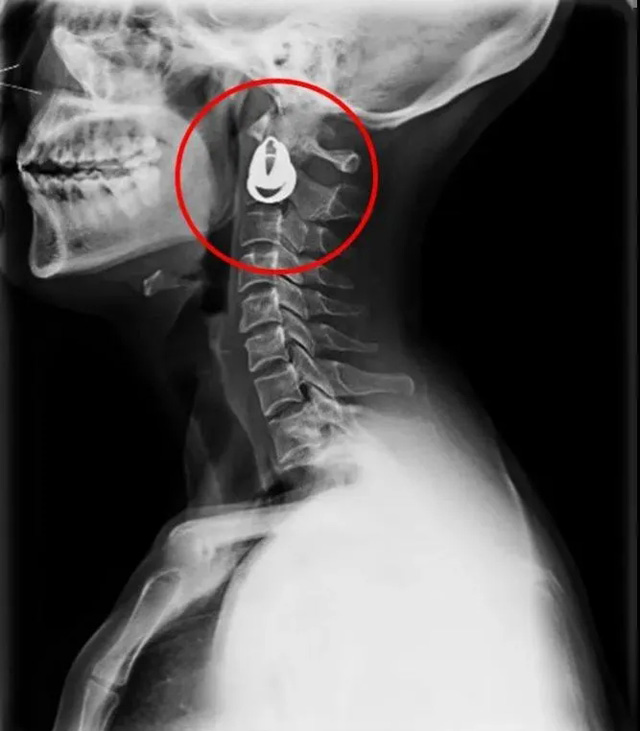

DR是一種比較常規(guī)的基礎(chǔ)影像學(xué)檢查方式,適用于人體各部位的健康普查及疾病檢查等優(yōu)勢,在臨床基礎(chǔ)檢查中備受醫(yī)生和患者的青睞。DR體檢車在健康體檢中有著非常重要的地位,由通過電纜串接在一起的探測板、掃描控制器、系統(tǒng)控制及影像顯示器等構(gòu)成。對比CT檢查而言,DR檢查的價格更低,輻射劑量更小它可以讓疾病預(yù)防,微細(xì)病變可更好顯示診斷治療提供科學(xué)的結(jié)果依據(jù)。很多外傷患者都要做DR檢查,來判斷是否骨折或其他的情況。體檢過程中面對DR體檢車做檢查時候需要準(zhǔn)備注意什么呢?很多時候大家都有這樣的疑問,身上攜帶的物品是否會對圖像造成遮擋或給機器帶來干擾?檢查前如何準(zhǔn)備才不會影響檢查準(zhǔn)確性?